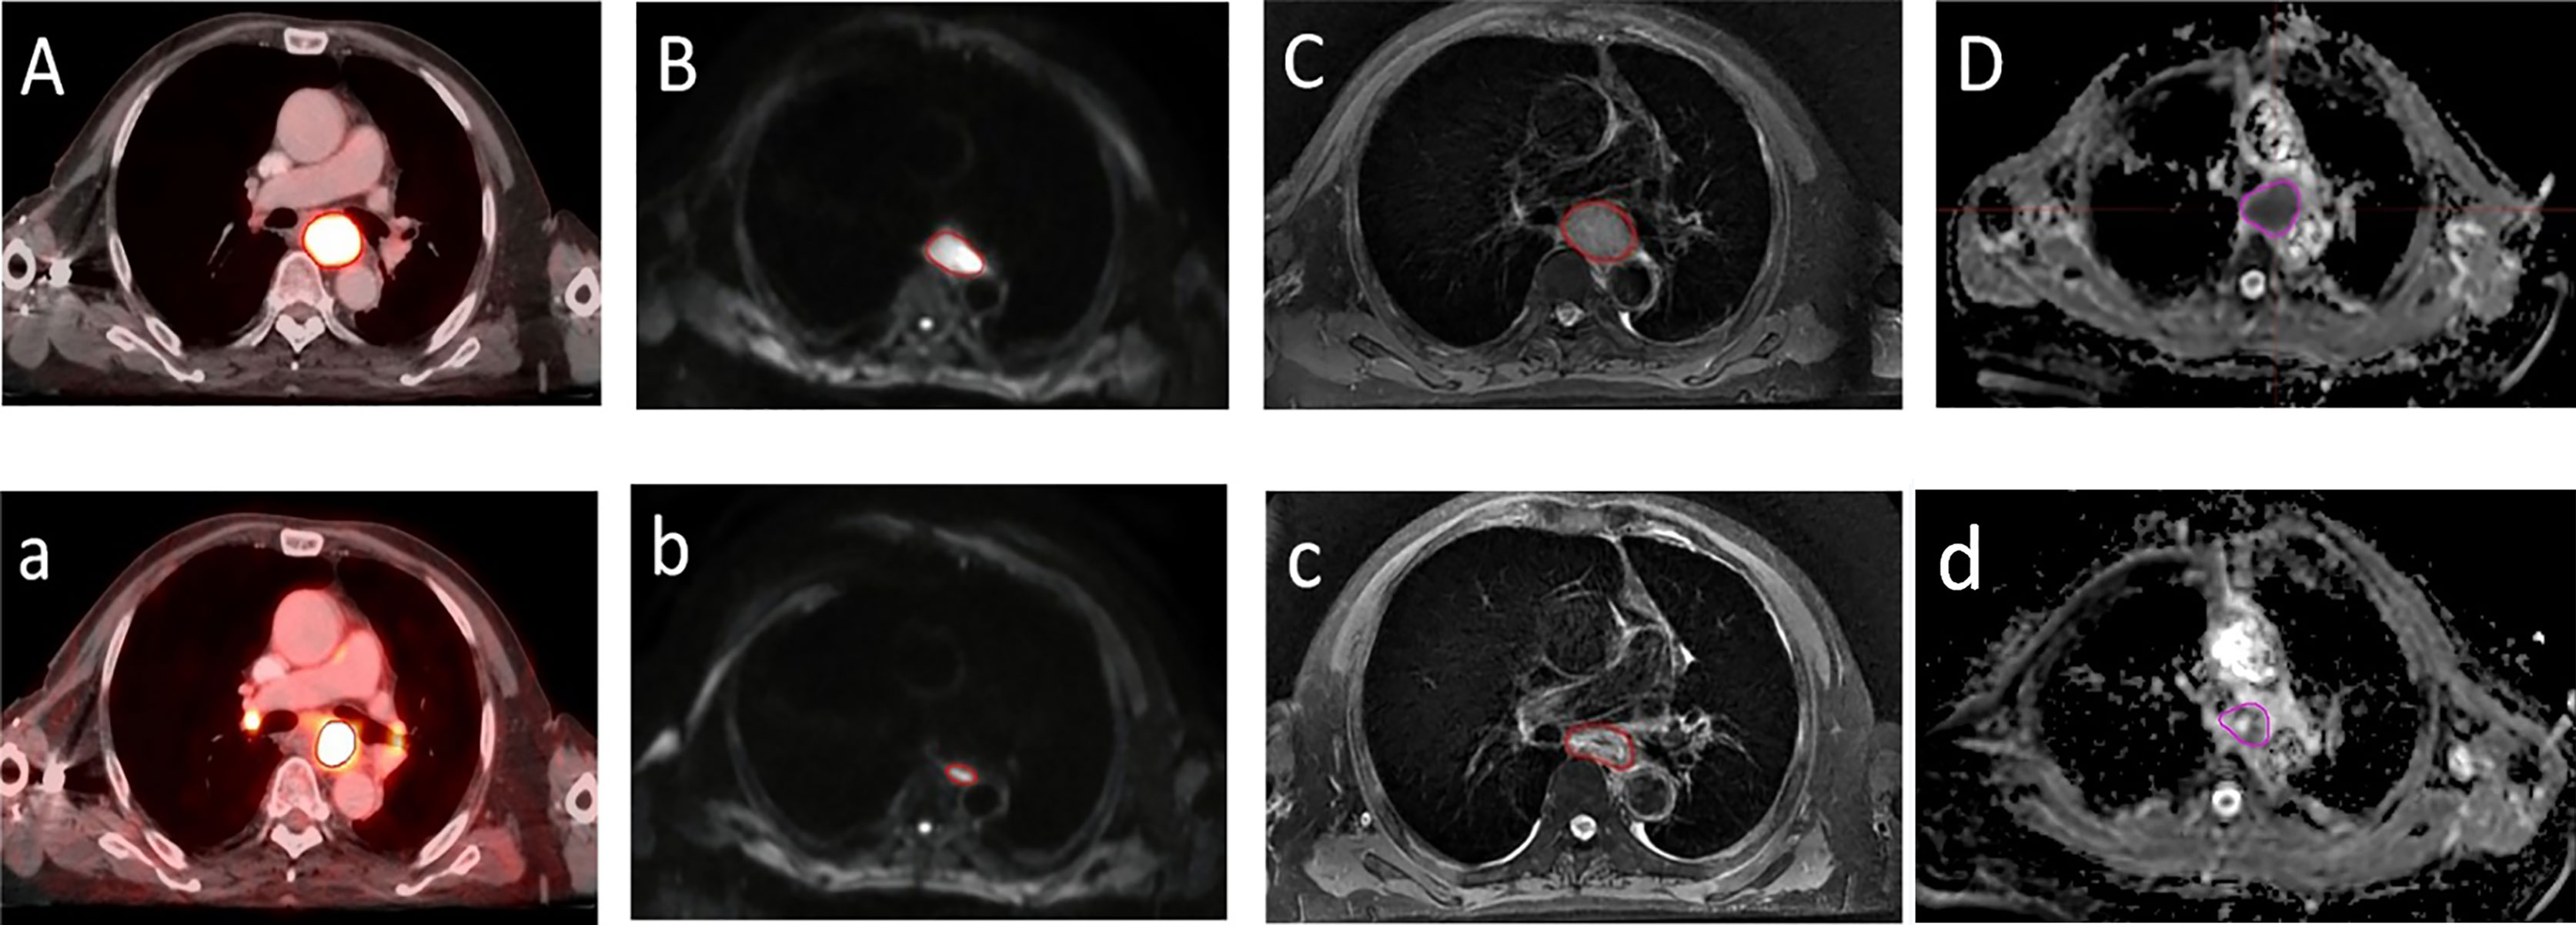

Tumor Maximum Diameter/Volume Shrinkage Rate

There was no significant difference between LDPETpre and LDDWIpre and between LDPETdur and LDDWIdur (median 2.85 cm [1.48−6.31] vs. 2.92 cm [1.89−5.33], median 2.36 cm [1.47−4.79] vs. 2.22 cm [1.35−3.47], Z = −1.169 and −1.187, p = 0.243 and 0.235, respectively). There was a significant positive correlation between LDPETpre and LDDWIpre and between VRRPET and VRRDWI (r = 0.631 and 0.547, p = 0.000 and 0.001, respectively). △LDDWI (24%) and VRRDWI (60%) based on DWI during RT were significantly greater than the corresponding PET-based △LDPET (14%) and VRRPET (41%) (Z = −2.393 and −3.758, p = 0.017 and 0.000, respectively) (Figure 2).

Figure 2 A transversal diagram of gross target volumes on esophageal cancer with high uptake on 18F fluorodeoxyglucose positron emission tomography/computed tomography fused images. (A,a) Corresponding tumor on T2-weighted imaging (C,c) with a high signal on diffusion weighted magnetic resonance imaging (b=600 s/mm2) (B,b) and corresponding apparent diffusion coefficient map (D,d) with restricted diffusion at the location of the tumor before radiotherapy (A–D) and during radiotherapy (a–d).

In addition, we evaluated the difference in matching and inclusion relation between the GTVs derived from PET-CT and DW-MRI simulation before and during RT. Our results indicate that the CI of GTVPETpre to GTVDWIpre was significantly larger than that of GTVPETdur to GTVDWIdur. Meanwhile, a significant difference was observed between the DI of GTVPETpre in GTVDWIpre and GTVPETdur in GTVDWIdur. Our study results are also consistent with the findings of Popp et al. (34) and Houweling et al. (35), who showed that the GTV of restricted diffusion on ADC overlapped only partially with that of increased glucose uptake for reirradiation treatment planning, suggesting that there were great mismatches between the regions of residual high FDG uptake based on PET-CT and the areas of residual high signal based on DW-MRI. Moreover, given the data from our study, the rate of tumor maximum diameter/volume regression based on DW-MRI during RT is significantly faster than that based on PET-CT. This suggests that the regions of high cellularity may not cover the entire biologically active tumor, agreeing with earlier studies comparing DWI and PET in reirradiation of recurrent primary brain tumors (34, 35).